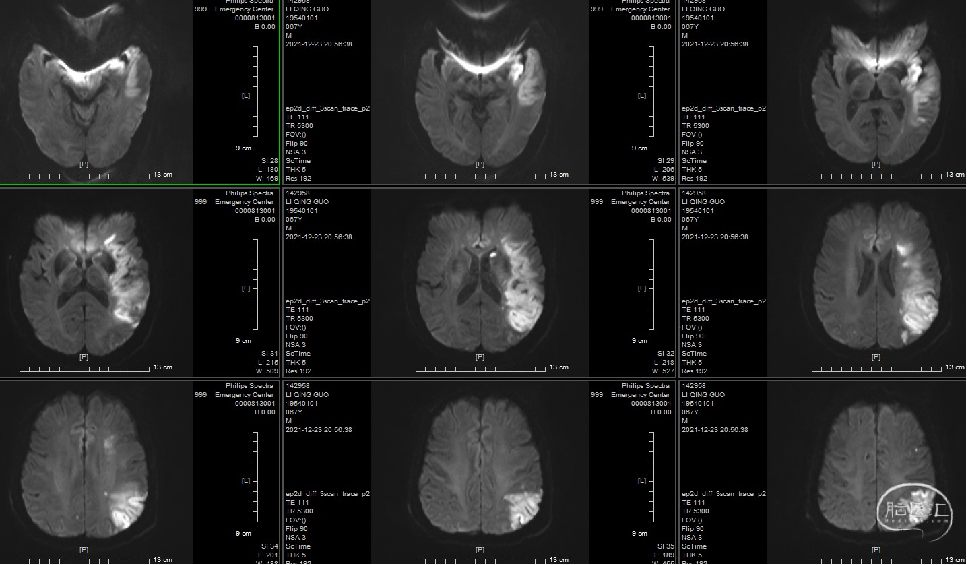

术后第二核磁(2021-12-23):左侧额叶、顶叶、颞叶、岛叶脑梗塞(急性-亚急性)

术后核磁明确该患者额叶、顶叶、颞叶、岛叶脑梗塞,但内囊及外缘部分皮层血流通畅,内囊恢复血流极大的帮助患者患肢快速恢复,同时额颞皮层保留使患者术前失语很快改善,目前可简单发声,如“谢谢”等。